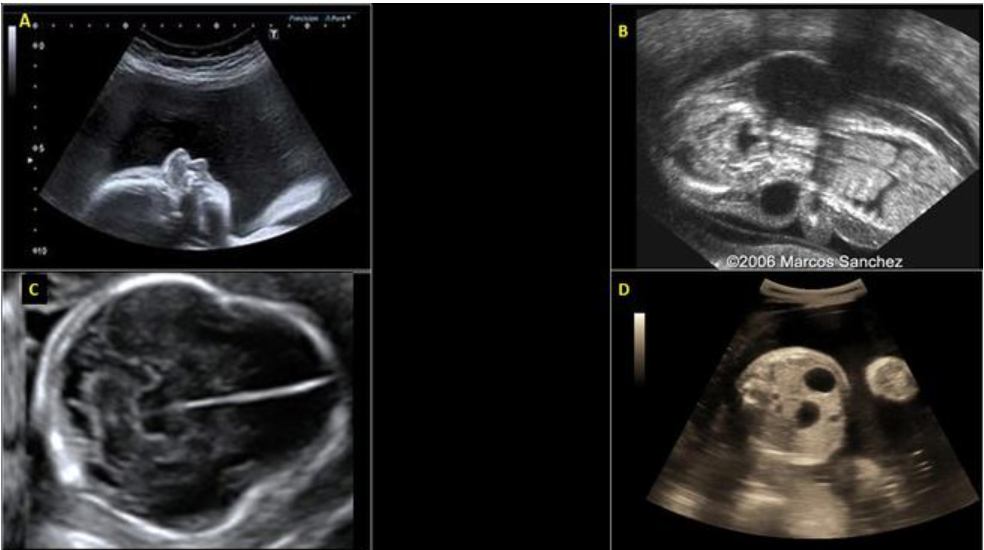

chorioangioma is supected. which image shows it

a) A

b) B

c) C

d) D